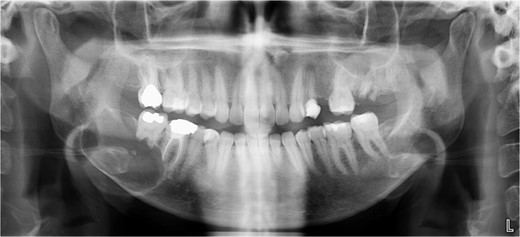

The excised specimen’s histopathology confirmed its benign nature. One year postoperatively, the patient showed no infection or inflammation, with optimal mouth opening and mandibular movement. The reconstruction plate remained stable and intact (Figs 6 and 7).

Postoperative panoramic radiograph demonstrating the reconstruction plate in place after tumor resection and bone grafting.

Follow-up panoramic radiograph showing stable reconstruction plate and no signs of recurrence one year postoperatively.